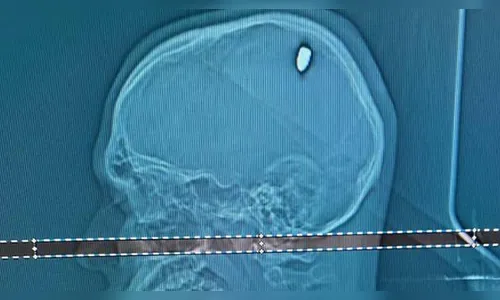

Era um projétil de 9 mm, alojado no crânio. "O que me disseram é que o cérebro percebeu que havia um corpo estranho naquele local, que estava começando a afetar o sistema nervoso, por isso a convulsão", conta.

"Parte dela penetrou no cérebro. Isso causou compressão da região e os movimentos involuntários no braço", afirmou ao Jornal Nacional, da TV Globo, Flávio Falcometa, responsável pela extração da bala na cabeça do jovem. Segundo o médico, por uma distância de poucos milímetros o projétil não causou um dano mais grave.